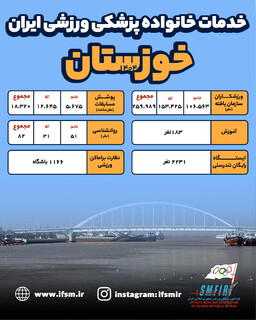

اینفوگرافیک/عملکرد سال ۱۴۰۴ هیات پزشکی ورزشی استان خوزستان

تشریح عملکرد سال ۱۴۰۴ هیات پزشکی ورزشی استان خوزستان توسط دکتر روزدار

عضویت ۲۶۰ هزار ورزشکار استان در کمیته خدمات درمانی فدراسیون پزشکی ورزشی

دکتر منصور روزدار رئیس هیات پزشکی ورزشی استان خوزستان عملکرد سال ۱۴۰۴ این هیات را تشریح کرد.